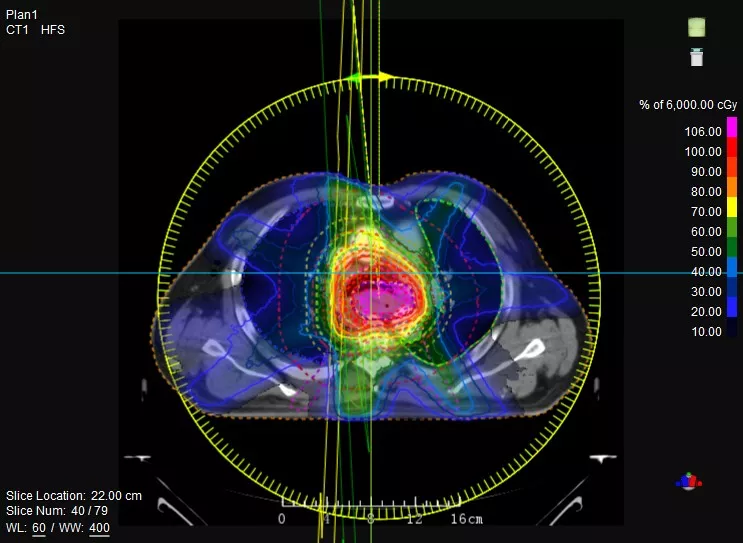

機(jī)載CT影像可直接用于放療計(jì)劃制作

鼻咽癌患者,進(jìn)行旋轉(zhuǎn)容積調(diào)強(qiáng)治療(uARC)